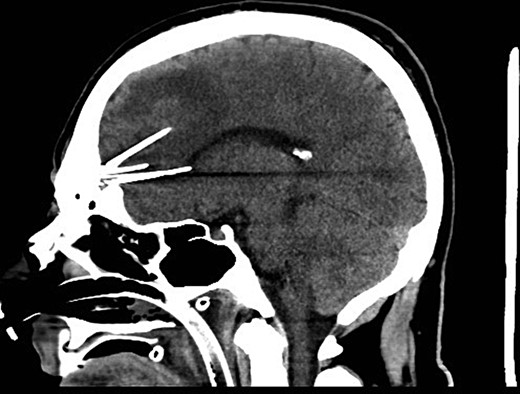

The patient had three postoperative seizures within 24 h of the surgery. He was commenced on phenytoin in addition to levetiracetam. The postoperative period was otherwise unremarkable. A postoperative CT was performed which demonstrated removal of all needles (Fig. 3). He was discharged home Day 3 with no further seizures. The patient remained seizure free at 6-month follow-up.

Sagittal postoperative CT scan demonstrating successful removal of the needles.